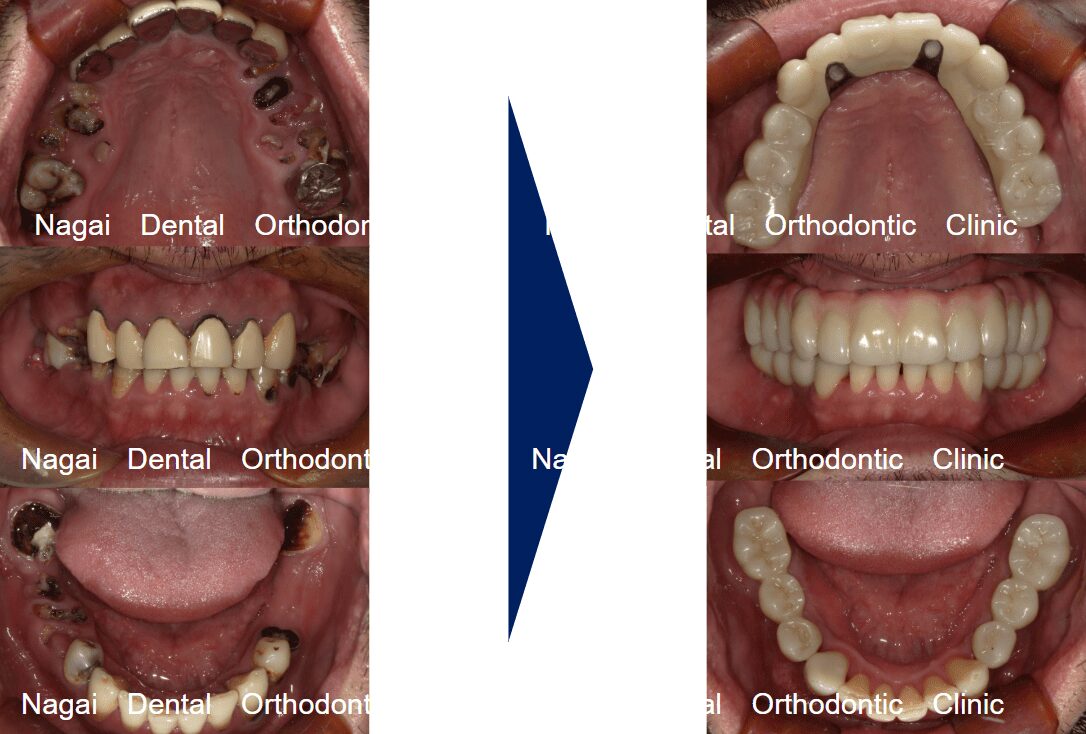

【口腔内の詳細変化】

▲再構築を目的とした治療を行いました

▲欠損していた左上奥歯部分の補綴完了状態

▲支持の安定が期待される治療を行いました

| 背景 | 多数歯欠損と咬合崩壊を主訴に来院。上顎は骨造成を回避し即日回復を目指したオールオンフォー、下顎は臼歯部インプラントによる再構成を選択しました。チタンフレームとジルコニアで耐久性と審美性を両立。術後は適切な噛み合わせにより咀嚼能率が向上し、機能・審美面ともに満足度の高い日常生活を取り戻されています。 |

| 治療期間 | 約5か月(通院8回) |

| 費用 | 5,384,400円(税込み) |